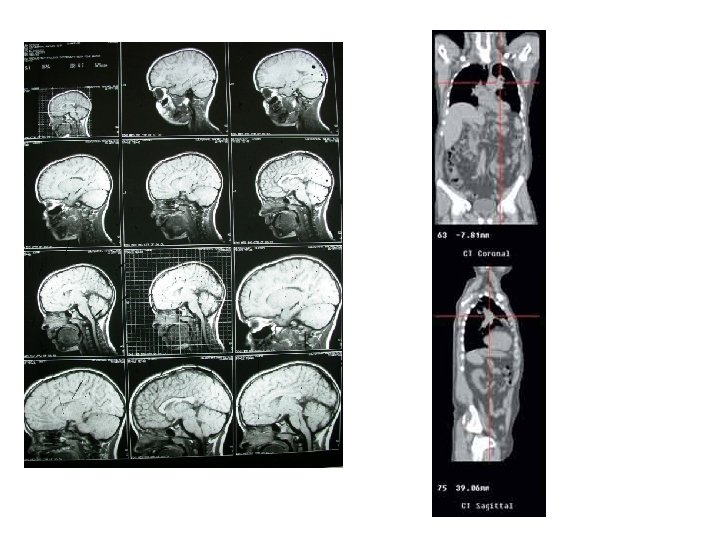

TOMOGRAFIA AXIAL COMPUTARIZADA • Consiste de un sistema de escaneo y detección, una computadora, y un medio de display. • Combina técnicas de reconstrucción de imágenes con medidas de absorción de rayos X. • Reconstruye todos los planos tomados en una imagen en 3 D

TOMOGRAFIA AXIAL COMPUTARIZADA • Se debe recolectar la mayor cantidad de información posible de la zona de interés para poder reconstruir la imagen. • Esto se logra girando el rayo de rayos X 360 y teniendo detectores fijos (hasta 700). • La idea es “fotografiar” pequeños cortes transversales que luego se reconstruyen en el volumen total.

TOMAGRAFIA AXIAL COMPUTARIZADA • Al girar alrededor del cuerpo obtiene múltiples imágenes. • La computadora combina estas imágenes en una imagen que representa una “rebanada” del cuerpo (podemos decir que es una radiografía de una rodaja del tejido en estudio). • Las imágenes se van sumando y luego se promedian, para obtener la imagen final de cada corte transversal. • De todos estos cortes se reconstruye una imagen en 3 D que puede observarse desde cualquier ángulo.

VENTAJAS • Provee información en 3 dimensiones de las estructuras internas del cuerpo (dando varios cortes transversales del área de interés) • La imagen que se obtiene es muy nítida • Es capaz de percibir diferencias pequeñas en los tejidos blandos • La dosis de radiación que se le aplica al paciente es menor que en los sistemas convencionales de rayos X